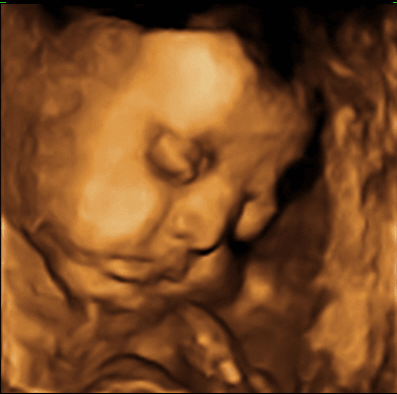

w sobotę u lekarza syn był głową w dół, więc byłam cała w skowronkach, a dziś na echo serca płodu wyszło, że jest zadkiem w dółtragedia normalnie, nie ma za dużo czasu na obroty już....